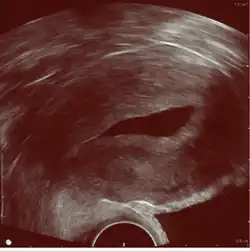

Sonohysterography. The sterile saline instilled into the cavity of the uterus is anechoic (rendered as dark in the middle of the image). It shows a normal endometrium as a hyperechoid (brighter) band around the cavity, in this case without any focal changes.

Sonohysterography is a specialized procedure by which fluid, usually sterile saline (then called saline infusion sonography or SIS), is instilled into the uterine cavity, and gynecologic sonography performed at the same time. A review in 2015 came to the conclusion that SIS is highly sensitive in the detection of intrauterine abnormalities in subfertile women, comparable to hysteroscopy. SIS is highly sensitive and specific test in the diagnosis of uterine polyps, submucous uterine fibroids, uterine anomalies and intrauterine adhesions (as part of Asherman's syndrome), and can be used as a screening tool for subfertile women prior to IVF treatment.[4]